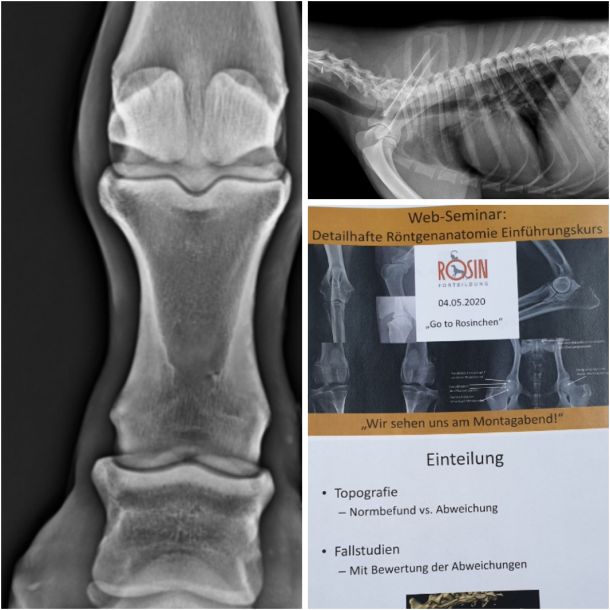

Röntgenanatomie Peter Rosin